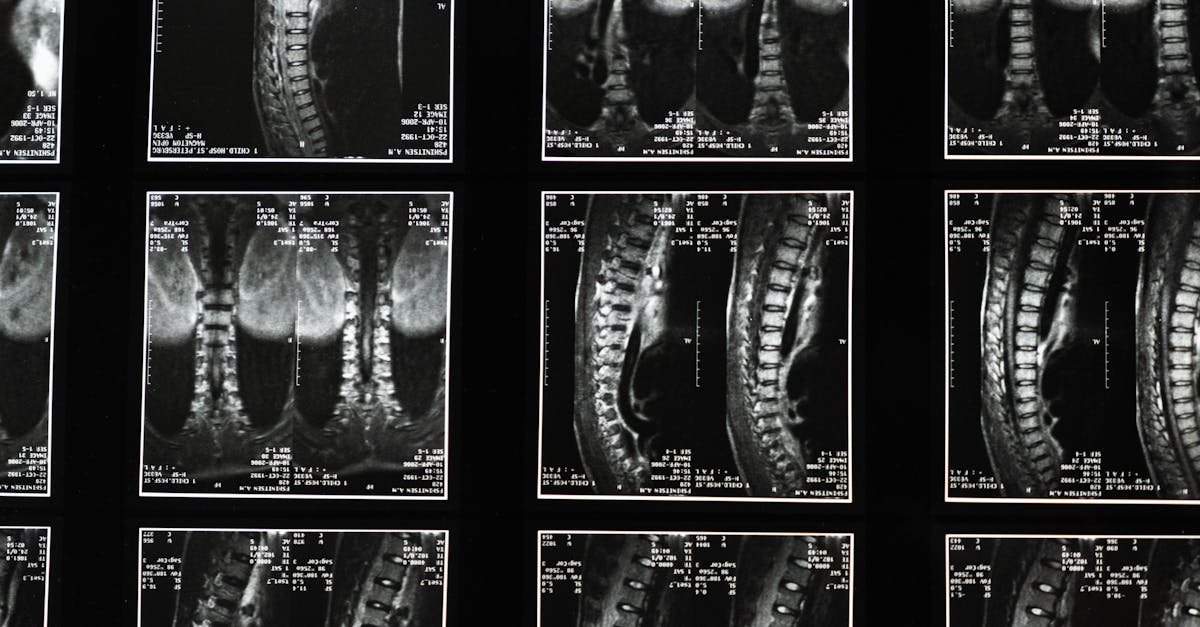

Sciatica is characterized by pain radiating along the path of the sciatic nerve, which runs from your lower back down through your hips and buttocks and down each leg. The common causes of this pain often include a herniated disc or lumbar pain that compresses the nerve. Understanding the root causes is crucial in addressing your lower back pain.

Sciatica is a condition caused by inflammation of the sciatic nerve, which can result in back pain, particularly in the buttocks or leg pain. This nerve originates in the lower back, runs down the back of each leg, and is responsible for providing movement and sensations in the legs and feet. The most common causes of sciatica are a herniated disc, lumbar spinal stenosis, or degenerative disc disease. These issues can compress the sciatic nerve, leading to the characteristic sciatic pain that radiates down the leg, potentially reaching the foot. Sciatica symptoms can vary, ranging from mild discomfort to severe pain, and can also include tingling, numbness, and muscle weakness.

TAGMED’s advanced Spinal Decompression Therapy offers a non-surgical solution specifically designed to address moderate-to-severe disc issues, including herniated discs, bulging discs, and spinal stenosis. By gently reducing pressure on the affected discs and nerves, this specialized technique enhances mobility, alleviates pain, and supports your body’s natural healing process. If you’ve reached a plateau with other therapies, discover how TAGMED’s evidence-based decompression approach can help you resume an active, comfortable life.

TAGMED’s neurovertebral decompression applies a controlled, progressive traction force to the spine. This advanced method increases the space between vertebrae, significantly reducing pressure on intervertebral discs and nerve roots. By promoting better fluid circulation in the targeted area, this process effectively lowers inflammation and relieves pain. As a result, individuals suffering from chronic back pain can experience a reliable, non-invasive solution to their issues.